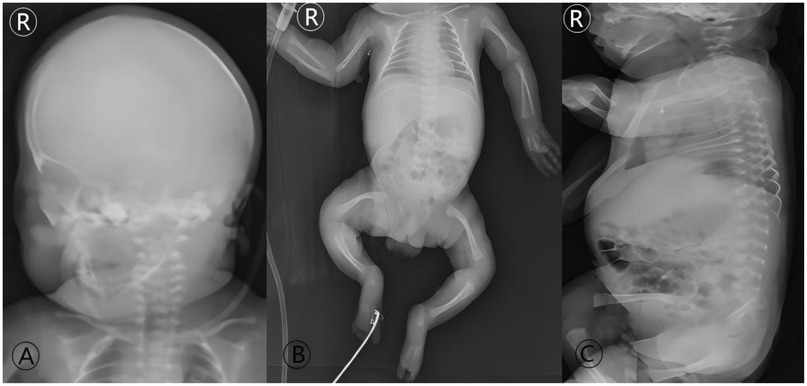

Background: Osteogenesis Imperfecta (OI) poses a unique challenge in pediatric trauma and critical care, where the fragility of bone intersects with life-threatening systemic complications, such as neonatal respiratory failure. The early postnatal period is particularly precarious, demanding a delicate balance between life support and fracture prevention. Case Presentation: A 9-day-old male neonate with prenatally diagnosed COL1A2 (c.1459G>A, p.Gly487Arg) mutation was admitted to our NICU for respiratory distress and pneumonia. He was the progeny of a father with OI, delivered via cesarean section at 34 weeks due to fetal skeletal deformities. Management and Outcomes: A proactive, multidisciplinary team (MDT) protocol was immediately implemented, focusing on non-invasive respiratory support, meticulous handling to prevent iatrogenic injury, and optimized nutrition. This approach successfully resolved his respiratory failure without any new fractures during the NICU stay. However, on the 16th day post-discharge, the infant sustained a spontaneous fracture of the right proximal femur. This was managed conservatively with a Pavlik harness. Follow-up revealed rapid callus formation by day 52 and complete union by day 136, showcasing the characteristic hyperplastic healing pattern of OI. Conclusion: This case underscores that a coordinated MDT approach is vital for stabilizing critically ill neonates with OI. The occurrence of a fracture shortly after discharge highlights the transition to home care as a period of extreme vulnerability. Empowering families with comprehensive education and ensuring continuity of care are as crucial as in-hospital management for improving long-term outcomes in these fragile infants.